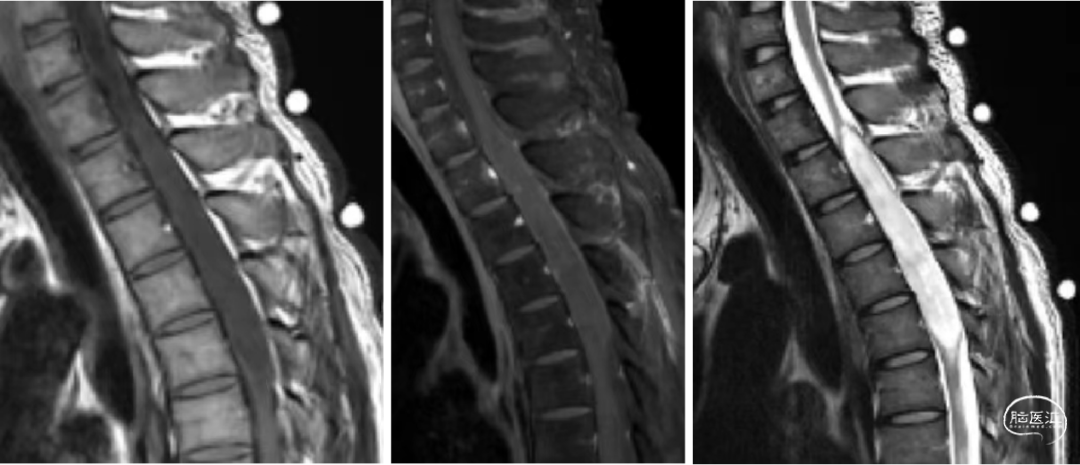

术前胸椎MR如下:

T1-6髓内病灶:室管膜瘤?